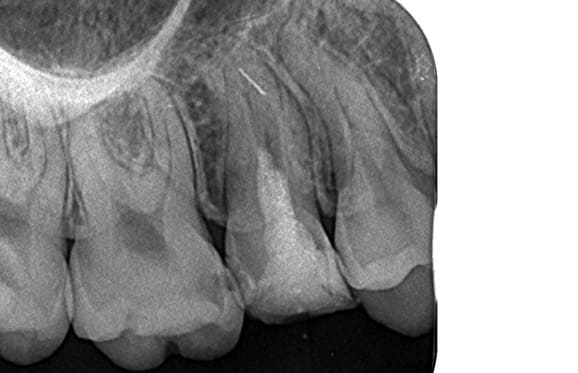

● C4を超え歯根までの虫歯を抜歯、親知らずを利用して歯並び全体を整えた症例

藤沢デンタルオフィスの虫歯や破折で抜歯後の部分矯正